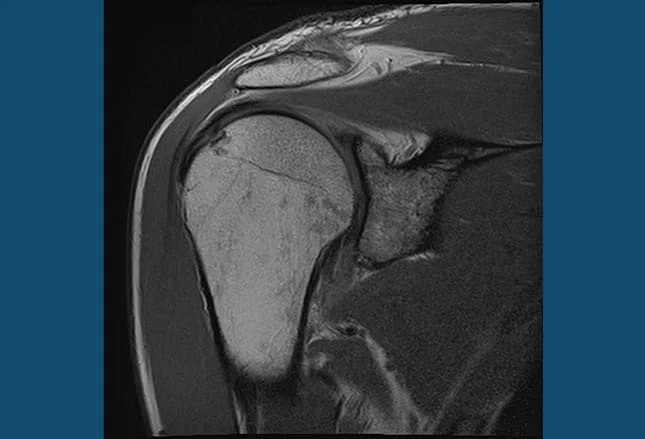

Thawing A Frozen Shoulder…with acupuncture

frozen shoulder